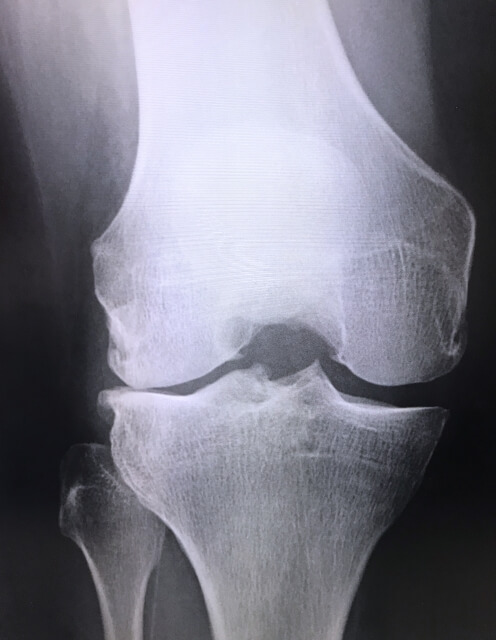

膝が痛くて病院へ行き、レントゲンを撮ると「膝が変形していますね」と言われることがよくあります。

「軟骨がすり減っていますね」とか...。

これは検査の結果、今の状態を伝えてくれているのです。

それをほとんどの方は「膝が痛いのは変形しているからだ」「軟骨がすり減っているから手術するしかないんだ」

と捉えてしまうのです。